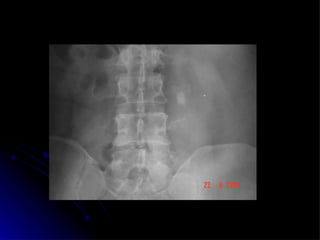

Lingeman JE; Surgical management of urinary lithiasis .  In Campbell´s Urology. 8 ed. 2002 7 cm x 5,5 cm

Definição e classificação Parcial Completo Lingeman JE; Surgical management of urinary lithiasis .  In Campbell´s Urology. 8 ed. 2002 Cálculo Coraliforme

Lingeman JE; Surgicalmanagement of urinary lithiasis . In Campbell´s Urology. 8 ed. 2002 7 cm x 5,5 cm

Definição e classificaçãoParcial Completo Lingeman JE; Surgical management of urinary lithiasis . In Campbell´s Urology. 8 ed. 2002 Cálculo Coraliforme

• #10 Poderia um cálculo destes ser removido por laparoscopia????? O que voces pensam????? Vamos abordar nestes 10 minutos a definição e classificação dos cálculos coraliformes, as indicações de cirurgia aberta, a técnica cirurgica ,experiencia mundial, resultados e por fim considerações finais.

• #11 Parcial - Cálculo na pelve renal que se extende para 2 grupos de cálices Completo - Cálculo na pelve renal que se extende para todos os grupos de calices maiores OU Cálculo ocupando no mínimo 80% do sistema coletor